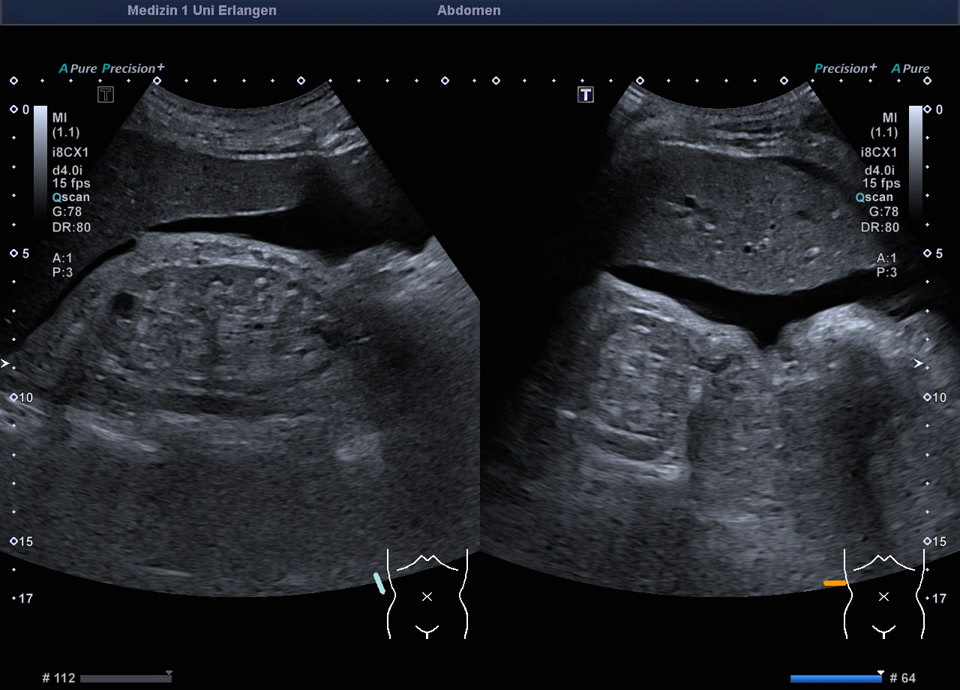

Chronische Nierenerkrankung

• Chronische Nierenerkrankung